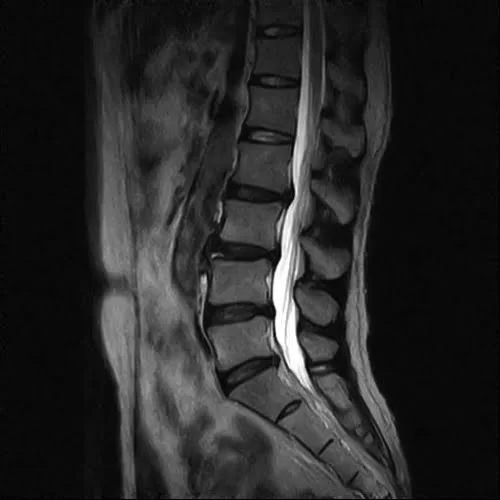

整形外科で撮っていただいたMRIの画像はこれ。

そもそもヘルニアとは?

椎間板ヘルニアに関して簡単に説明すると

こんな感じで骨と骨の間に軟骨があります。

そして腰骨の周りには神経がいっぱい走っているのです。

そんな場所でこんな感じで軟骨が飛び出して神経に触れると

痛みやシビレが出る。それが一般的なヘルニアだと思って下さい。

MRIの検査ではヘルニアの状態が確認出来ているので

誤診ということは無いと思います。

ヘルニアは飛び出した軟骨が神経に触れているから

腰や足に痛みやシビレが出ると言われるのですが。。。

今回のお客様の例で考えると

飛び出した軟骨が施術で元に戻って痛みが消えたのか

そもそも飛び出した軟骨と腰や脚の痛みは関係ないのか

ご判断はお任せいたします。